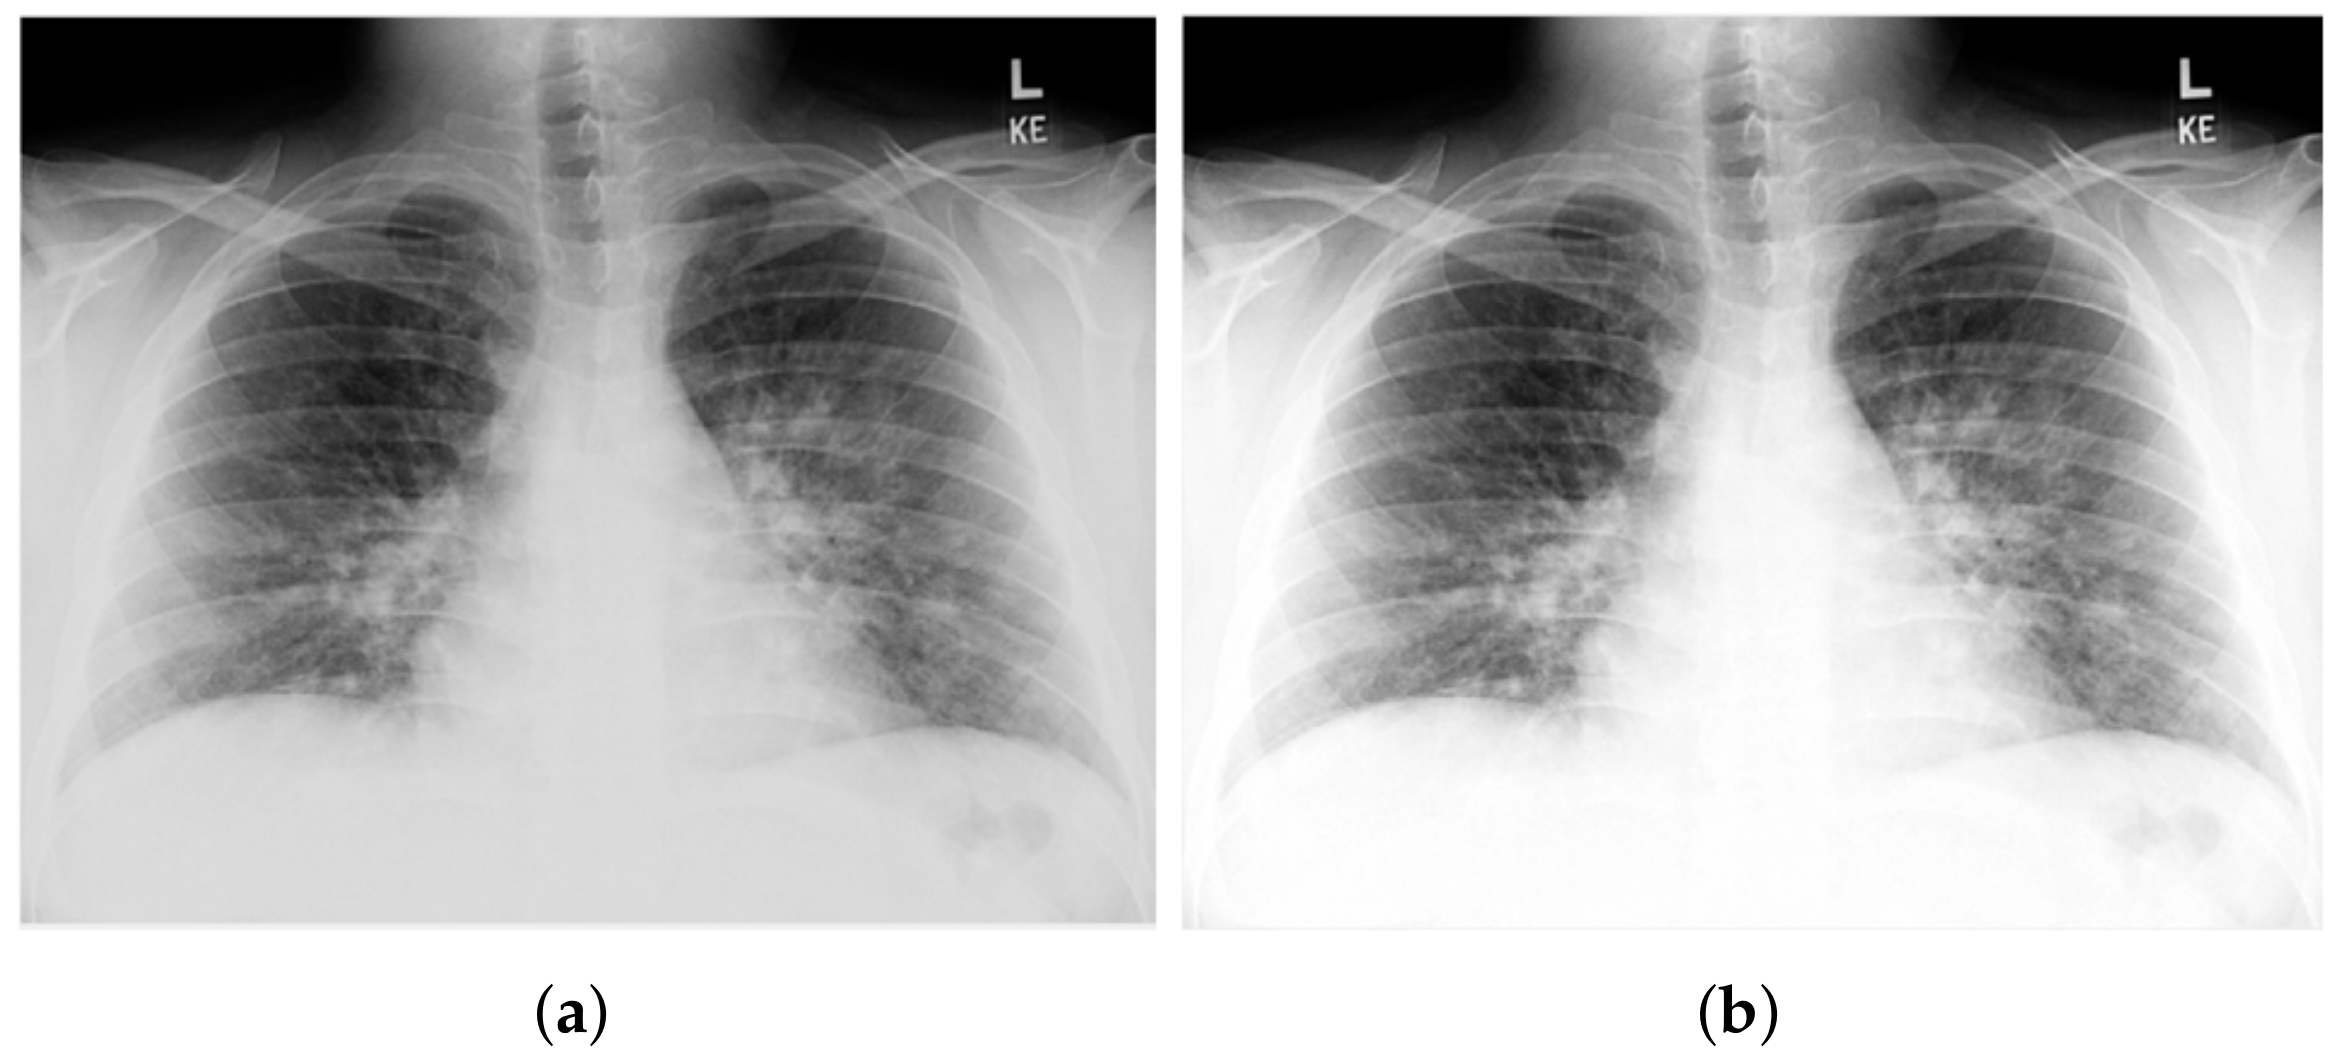

3.1. COV-PEN Image Datasets

3.2. Image Preprocessing Step